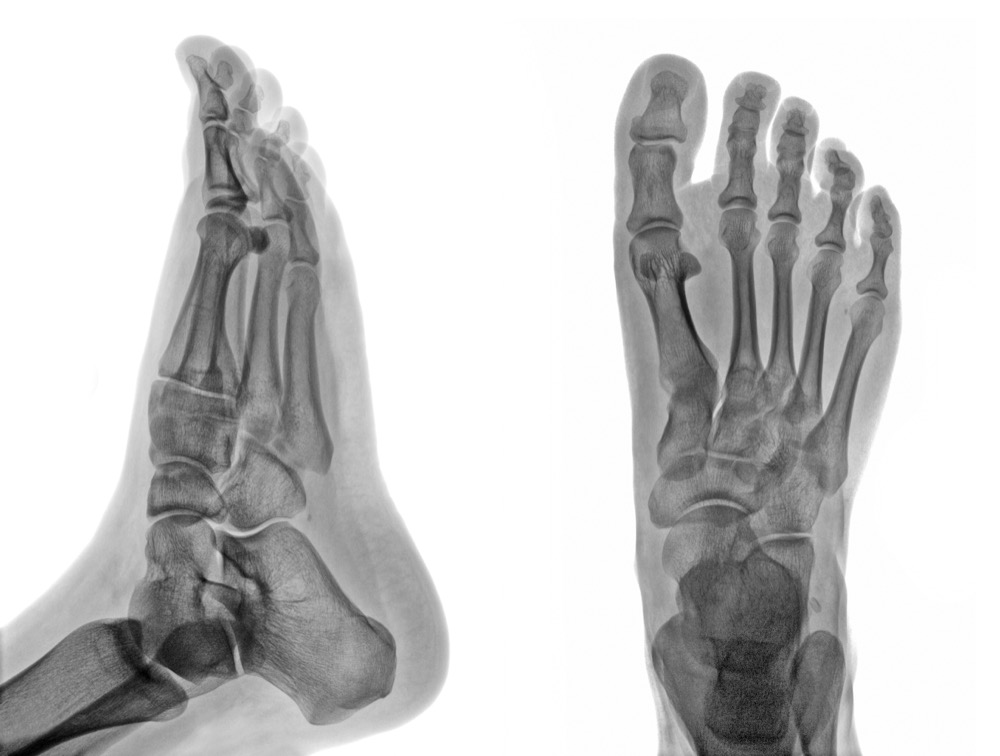

Our on-site digital x-ray system provides immediate, high-resolution images of bones and joints in the foot and ankle. Digital imaging offers lower radiation exposure than traditional x-rays, and results are available in minutes — allowing Dr. Quach to diagnose fractures, arthritis, deformities, and other conditions during your visit.

Having digital x-ray capability on-site is a significant advantage for our patients. Rather than scheduling imaging at a separate facility and waiting for results, we can take and analyze x-rays during your appointment — allowing Dr. Quach to diagnose conditions and begin treatment in a single visit. Our McAllen office is equipped with digital radiography.

Digital x-rays are used to diagnose a wide range of foot and ankle conditions including fractures, stress fractures, arthritis, bone spurs, joint dislocations, bunion and hammer toe deformities, and foreign bodies. They are also essential for pre-surgical planning and post-operative follow-up to monitor bone healing and hardware placement.